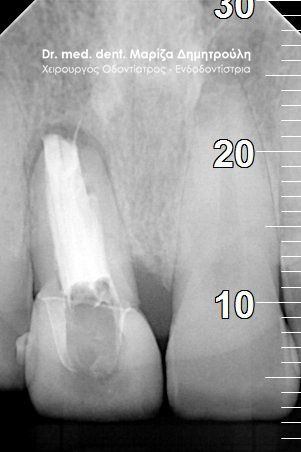

Περιστατικό – Επανάληψη απονεύρωσης δοντιού

Ο ασθενής παραπονείται για έναν μόνιμο πόνο στην περιοχή του αριστερού ιγμορείου. Ανέφερε οτι πριν χρόνια πραγματοποιήθηκε στον αριστερό γομφίο (τραπεζίτη) μία απονεύρωση. Μετά από καιρό εμφανίστηκαν τα συμπτώματα πόνου, χωρίς καμία βελτίωση. Μετά τον αποκλεισμό της ανάμειξης του ιγμορείου στη εμφάνιση των συμπτωμάτων ακολούθησε η κλινική και ακτινογραφική εξέταση του δοντιού. Η ακτινογραφία αποκάλυψε την ατελή απονεύρωση του δοντιού.

Μετά από συνεννόηση με τον ασθενή αποφασίστηκε η επανάληψη της ενδοδοντικής θεραπείας (απονεύρωσης). Ακολούθως έγινε τοποθέτηση του ελαστικού απομονωτήρα, η διάνοιξη του δοντιού και η αφαίρεση του παλιού εμφρακτικού υλικού από τις ρίζες.Επιπρόσθετα εντοπίστηκε και παρασκευάστηκε και 4ος ριζικός σωλήνας, ο οποίος δεν είχε επεξεργστεί στην πρώτη ενδοδοντική θεραπεία ( απονεύρωση ) του ασθενούς.

Διαπιστώθηκε η ενσβεστίωση 2 ριζικών σωλήνων του δοντιού (ριζών), κάτι που δεν επέτρεψε την επεξεργασία του δοντιού σε όλο το μήκος αυτών των ριζών. Παρολ΄ αυτά μετά τη δεύτερη συνεδρία ο ασθενής ανέφερε την ανακούφιση και την εξάλειψη των συμπτωμάτων, που τον ταλαιπωρούσαν τα τελευταία χρόνια.

Εφόσον το δόντι ήταν ασυμπτωματικό και ο ασθενής δεν αισθανόταν πλέον πόνο ολοκληρώθηκε η διαδικασία της απονεύρωσης με τη χρήση των μηχανοκίνητων εργαλείων και την τελική έμφραξη των ριζών του δοντιού με νέο εμφρακτικό υλικό.

ΠΡΙΝ

ΜΕΤΑ